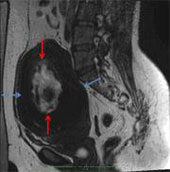

Abdominal CT scan showed a fundal fibroid measuring 12.9 x 11.0 cm, with areas of internal degeneration. MRI showed a hypointense fibroid on T2 weighted images, measuring 12.9(TR) x 14.0(SI) x 9.3(AP) cm, with a large central area of degeneration within (Fig. 1).

Fig. 1 – T2 weighted sagittal image showing a large fundal hypointense fibroid (blue arrows), with a central area of hyperintensity, representing internal degeneration (red arrows).